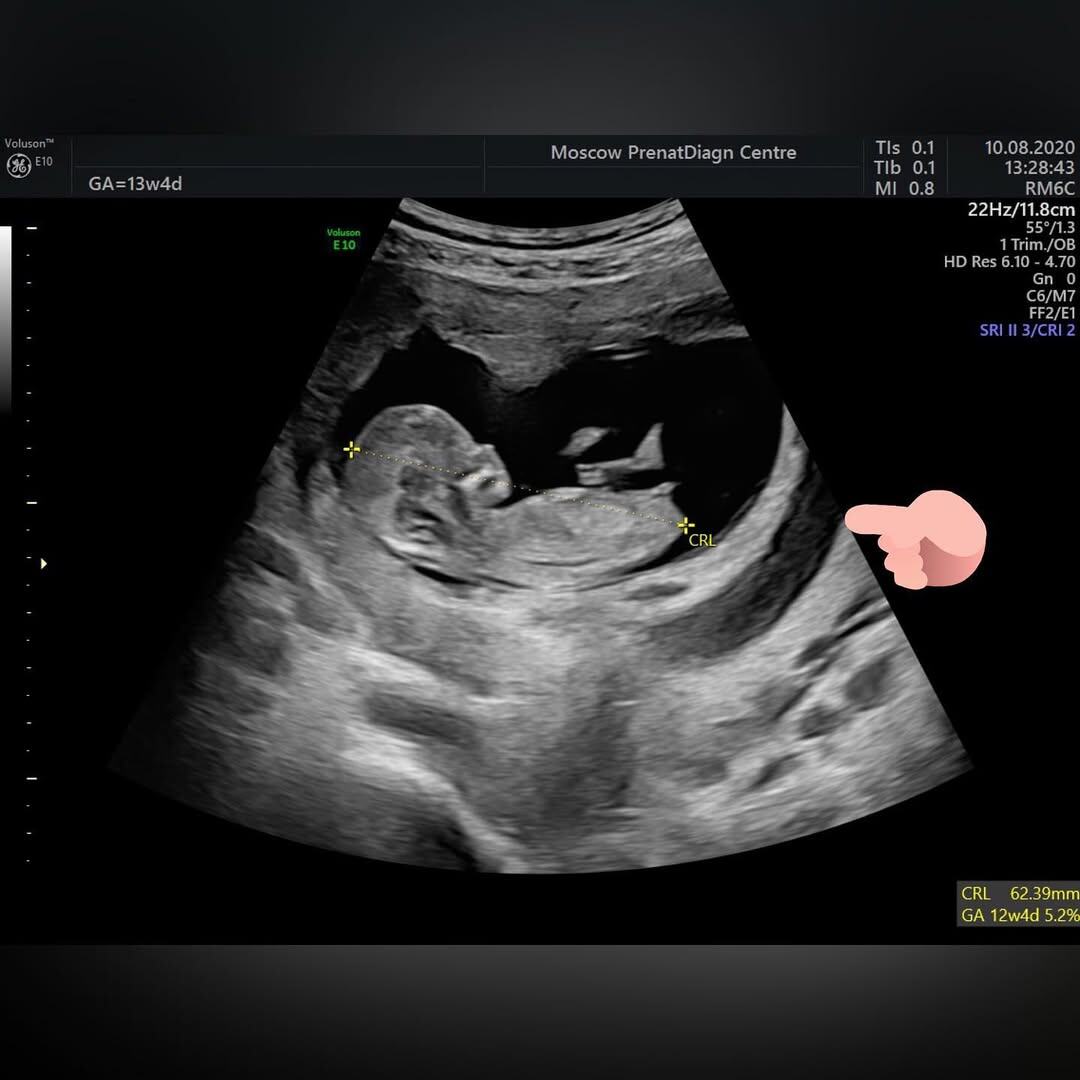

К нам Аня пришла в 13 недель. Испуганная, напряженная. Когда к тебе приносят такую историю, честно — браться страшно. Хочется зажмурить глаза и сказать «я в домике», как в детстве. Но я не «в домике», я — в клинике экспертной гинекологии, поэтому надо разбираться.

Картинка на УЗИ выглядит страшненько. Плодное яйцо буквально плавает в луже крови, но плод при этом бодр и весел. Это не ретрохориальная гематома, которая отслаивает и изгоняет плодное яйцо, а хориоамниотическая сепарация — ХАС.

Во время эмбрионального развития хориальная и амниотическая оболочки возникают из разных зародышевых листков, а затем сливаются между собой к сроку 14 -16 недель беременности, формируя единую хориоамниотическую мембрану. Иногда слияния оболочек может не происходить, такие случаи в основном описаны при хромосомных аномалиях, в основном анеуплоидиях (трисомии 21, 13 и 18) и расстройствах формирования соединительной ткани у плода.

Если оболочки слились, но по каким-то причинам вновь отделились друг от друга, речь идет о хориоамниотической сепарации — ХАС. Это явление, когда происходит разделение уже сформировавшейся мембраны на плацентарную (хориальную) и плодовую (амниотическую) оболочки.

Выделяют полную и частичную ХАС. При частичной ХАС разделение обнаруживается на небольшом участке, при полной возникает расслоение оболочек на всем протяжении, за исключением места впадения пуповины в плаценту.

Чаще всего причиной ХАС бывает проведение инвазивных процедур, таких как амнио-, кордоцентез и фетальная хирургия. В зависимости от типа вмешательства ХАС может происходить во 2 и 3 триместре. Спонтанные ХАС встречаются редко, иногда возникают к концу 1 триместра, практически сразу после слияния, и их причина пока неизвестна.